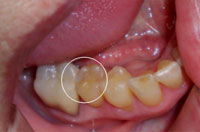

2. Carie on molar

Carie sur molaire

before treatment